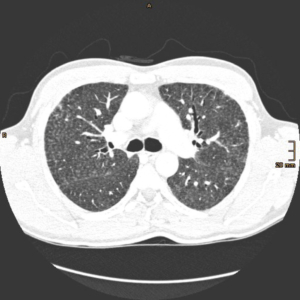

Richtungsweisend ist sicherlich die radiologische Bildgebung (HRCT) mit den typischen Befunden der Akutphase wie zentrilobuläre Noduli, Milchglasopazitäten, Airtrapping in Exspiration und in der chronischen Phase zusätzlich Retikulationen und Traktionsbronchiektasen [7].

Da die Diagnosestellung knifflig sein kann, liefern die Autoren Raghu et al. [7] ein Flussdiagramm, welches die Kriterien der passenden Anamnese, HRCT- Bildgebung, Labor, BAL und Histopathologie inkludiert.